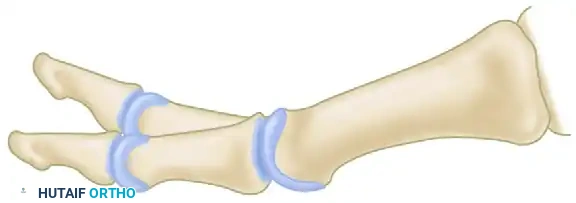

مع تقدم المرض واستمرار الاحتكاك العظمي، يمتد تآكل الغضروف هذا إلى المركز، وفي النهاية يشمل الجانب الأخمصي (السفلي) لرأس المشط. بالتزامن مع تآكل الغضروف، واستجابة للاحتكاك والضغط غير الطبيعي، يبدأ الجسم في محاولة إصلاح نفسه بشكل خاطئ، مما يؤدي إلى تكوّن نتوءات عظمية حادة (Osteophytes) حول حواف المفصل.

هذه النتوءات العظمية تعمل كمصدات ميكانيكية تمنع الإبهام من الانثناء لأعلى (Dorsiflexion) أثناء المشي، مما يسبب ألماً حاداً وتقلصاً شديداً في نطاق حركة المفصل. هذا التطور تدريجي ولكنه لا هوادة فيه، وقد ينتهي بتيبس كامل للمفصل.

3. العظام السمسمية (Sesamoid Bones)

وهما عظمتان صغيرتان تشبهان بذور السمسم، تقعان أسفل رأس المشط الأول (في الجانب الأخمصي) داخل وتر العضلة المثنية القصيرة لإبهام القدم. وظيفتهما الأساسية هي امتصاص الصدمات، تقليل الاحتكاك، وزيادة القوة الميكانيكية للأوتار أثناء مرحلة الدفع في المشي.